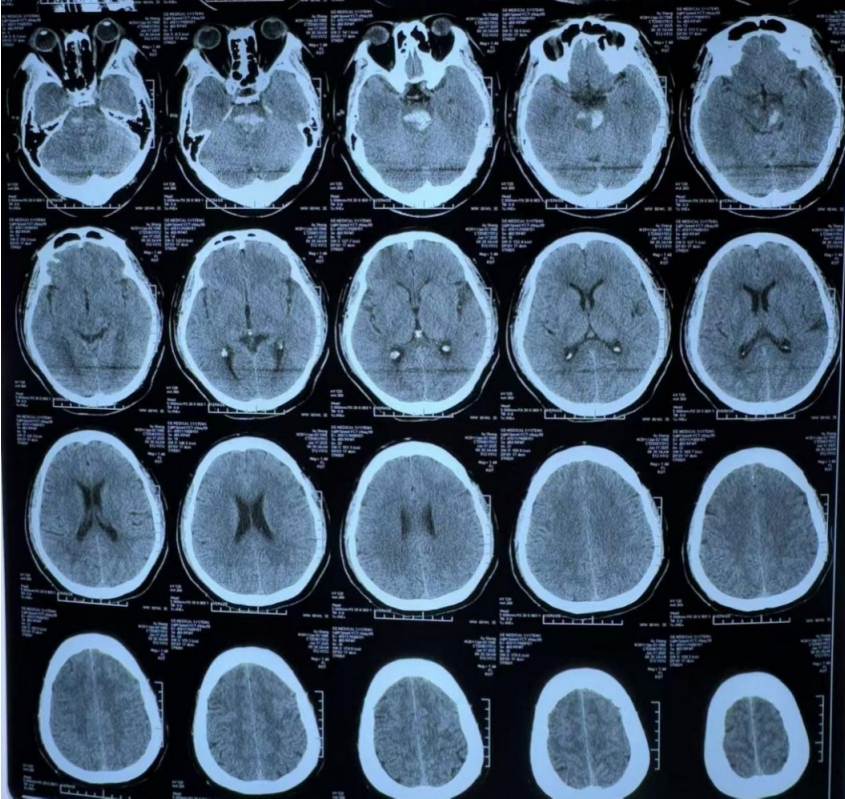

入院时,患者已处于昏迷状态,并丧失自主呼吸,瞳孔缩小光反射消失。为了维持呼吸道通畅,紧急实施了气管插管。随后头部CT扫描显示,吴先生患有脑干出血,出血量大约为8毫升,情况十分凶险。

(术前CT:脑干出血)